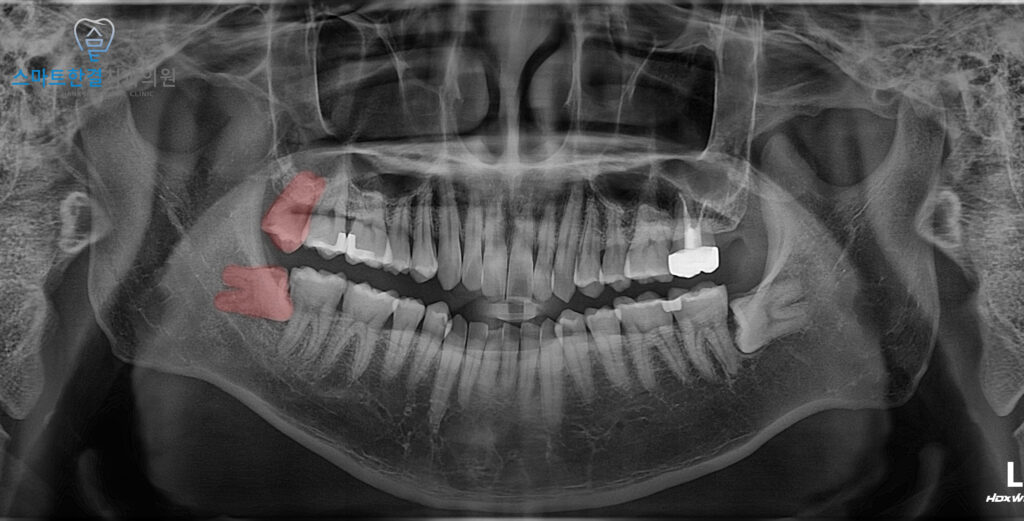

위 환자분께서는

오른쪽 위, 아래 사랑니

발치를 진행했는데요.

환자분께서는 아래 사랑니가

옆 치아를 미는 거 같고,

잇몸에 염증이 생겨 붓고 불편함에

본원에 내원해 주셨어요.

아래 사랑니는 완전히 누운 채 자라

머리 일부만 드러난 상태였고,

앞 치아와의 사이에 음식물이 끼어

잇몸이 부어 있었어요.